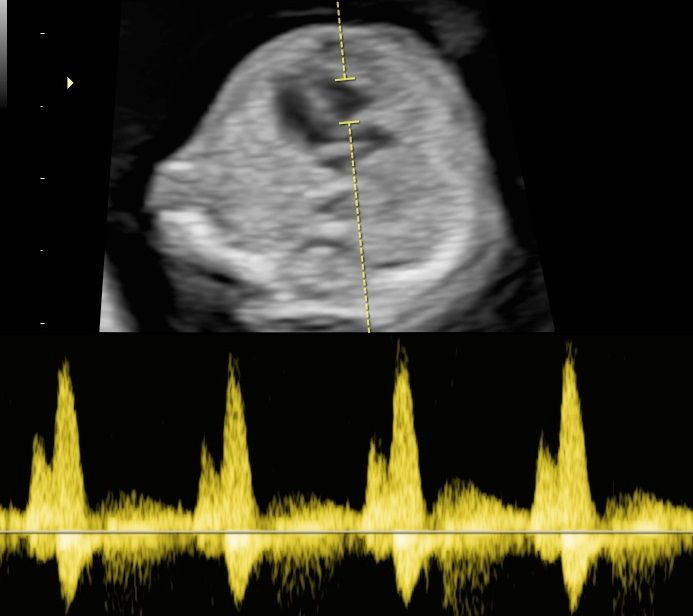

-certyfikat The Fetal Medicine Foundation (FMF) w zakresie badań prenatalnych w 11–13+6 tygodniu ciąży – przezierność karku u płodu (NT); kość nosowa u płodu (NB); przepływ w przewodzie żylnym u płodu (DV); przepływ na zastawce trójdzielnej (TR) oraz oceny ryzyka wystąpienia preeklampsji (stanu przedrzucawkowego) w ciąży.

Od 2022 współpracuje z Zakładem Kardiologii Prenatalnej ICZMP w Łodzi (pod kierownictwem prof Marii Respondek-Liberskiej) w zakresie diagnostyki i dalszej opieki specjalistycznej nad płodami z wrodzonymi wadami serca.

Zdjęcia i filmy